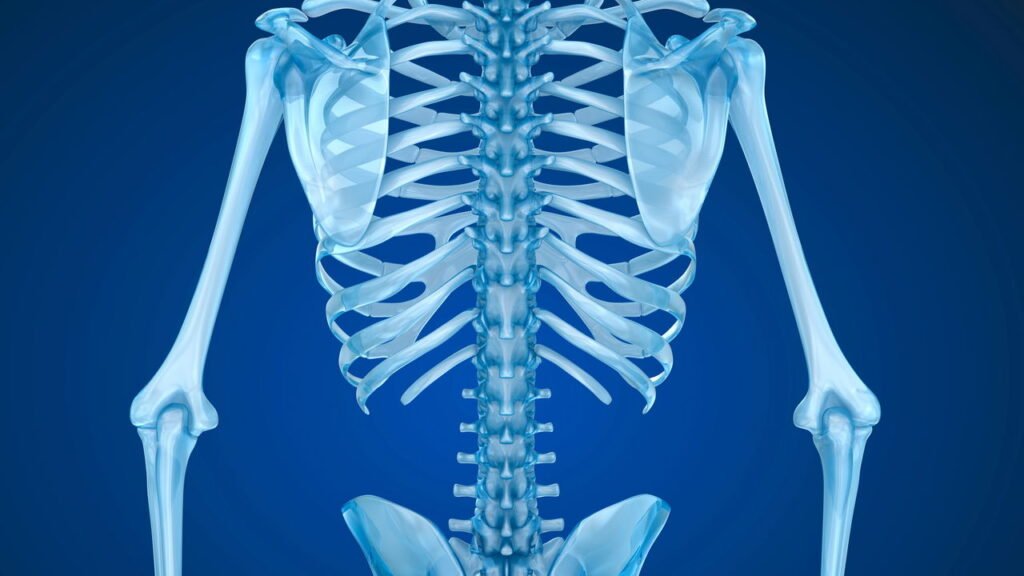

A saúde óssea é vital, especialmente com o envelhecimento. Além da nutrição (cálcio e vitamina D), a ciência comprova que o exercício físico é fundamental para fortalecer os ossos e prevenir a osteoporose. Este artigo explora a relação entre exercício e saúde óssea, mostrando como o movimento, especialmente exercícios de impacto e força, fortalece o esqueleto.

Os ossos são tecidos vivos em constante remodelação óssea, um processo de remoção de osso velho e formação de osso novo. O exercício, principalmente de impacto e força, estimula essa remodelação, fortalecendo a estrutura óssea.

Ao nos exercitarmos, a carga e tensão nos ossos sinalizam para os osteoblastos (células ósseas) produzirem osso novo. Isso resulta em ossos mais densos, fortes e resistentes, reduzindo o risco de fraturas.